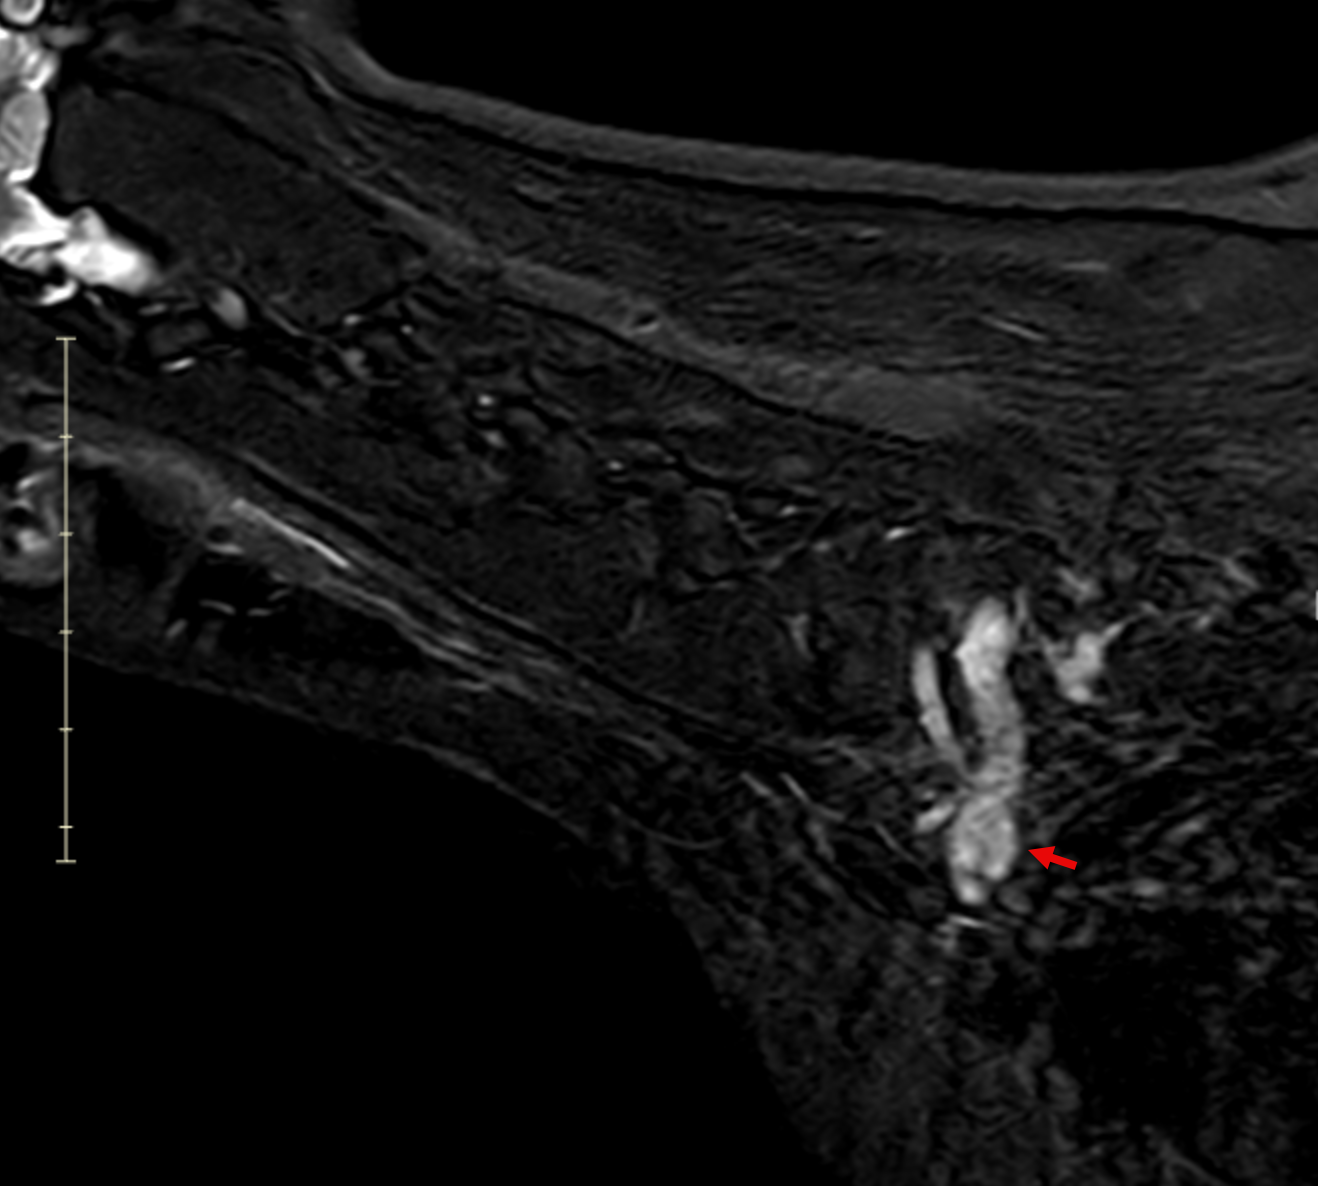

Image 5. Dorsal post-contrast MRI of the cervical spine and thoracic inlet demonstrating a contrast-enhancing lesion associated with the left-sided C7–T1 nerve roots extending into the brachial plexus.

Image 6. Sagittal post-contrast MRI demonstrating a tubular, contrast-enhancing mass extending along the left cervical nerve roots into the brachial plexus, with associated spinal cord compression.

MRI revealed a clinically significant and previously undetected diagnosis (Images 5-7):

Primary Diagnosis: Nerve Sheath Tumor

• Contrast-enhancing mass involving the left C7, C8, and T1 nerve roots

• Extension from the spinal canal through the intervertebral foramen into the axilla and brachial plexus

• Severe spinal cord compression with displacement

• Expansion of the C7–T1 neural foramen

• Associated neurogenic muscle atrophy of the left forelimb (triceps)